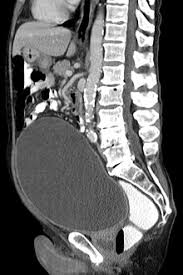

Wenn die Blase nicht vollständig entleert werden kann bleibt der sogenannte Restharn zurück. Warten Sie erst einmal die Zertrümmerung ab alles weitere können Sie den behandelnden Urologen fragen. Ihre Blase sollte nicht zu voll sein.

Das Gefühl die Blase nicht vollständig entleert zu haben begleitet die Betroffenen meist direkt nach dem Toilettengang und führt dazu dass sie nach kurzer Zeit erneut die Toilette aufsuchen müssen. Normalerweise scheiden Erwachsene täglich je nach Trinkmenge ca. Wenn du sie tatsächlich nicht komplett entleeren kannst solltest du das auf jeden Fall mal beim Urologen abklären lassen.

Wenn du häufig das Gefühl hast die Blase nicht richtig entleeren zu können bzw. Eine Blasenentleerungsstörung ist eine Abflussstörung des Urins aus der Harnblase. Stellen Sie sicher dass Sie sorgfältig die erhaltenen Anweisungen zur Vorbereitung und Durchführung der Katheterisierung befolgen.